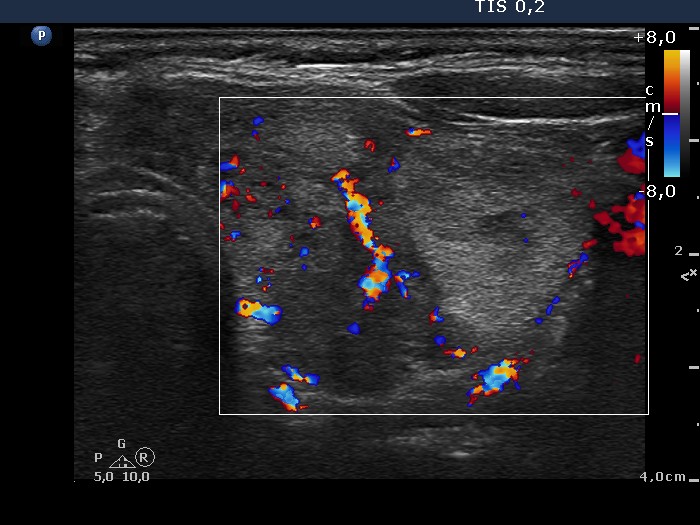

Right lobe, longitudinal scan

Left lobe, transverse scan, color Doppler mode. The nodule displays perinodular blood flow.